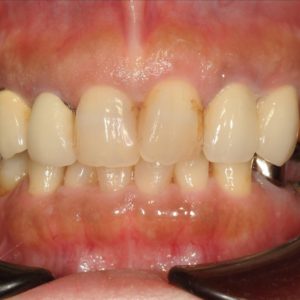

虫歯の治療、矯正の相談をご希望され来院されました。お口の中を診査(レントゲン写真、口腔内写真、視診)させていただいたところ、虫歯については問題なくきれいに歯磨きされているようでした。 正面から見るとジグザグしており、お口 […]

全体的な歯並びの矯正治療を行いました。治療期間は3年間。

ジグザグの歯並びを気にされてご来院されました。. 見た目の問題も大切ですが、それ以上に清掃がしにくいために虫歯・歯周病に非常になりやすく、不正咬合(良くないかみ合わせ)は顎の関節に負担をかけてしまい顎関節症を引き起こす可 […]

歯の大きさに対する顎の大きさのスペース不足により歯が並びきらず、ジグザグの歯並びおよび上の前歯が出っ歯になっていました。 左右4番の歯を抜歯することにより歯を並べるスペースを確保し、歯並びを揃えました。 全体の歯並びが綺 […]